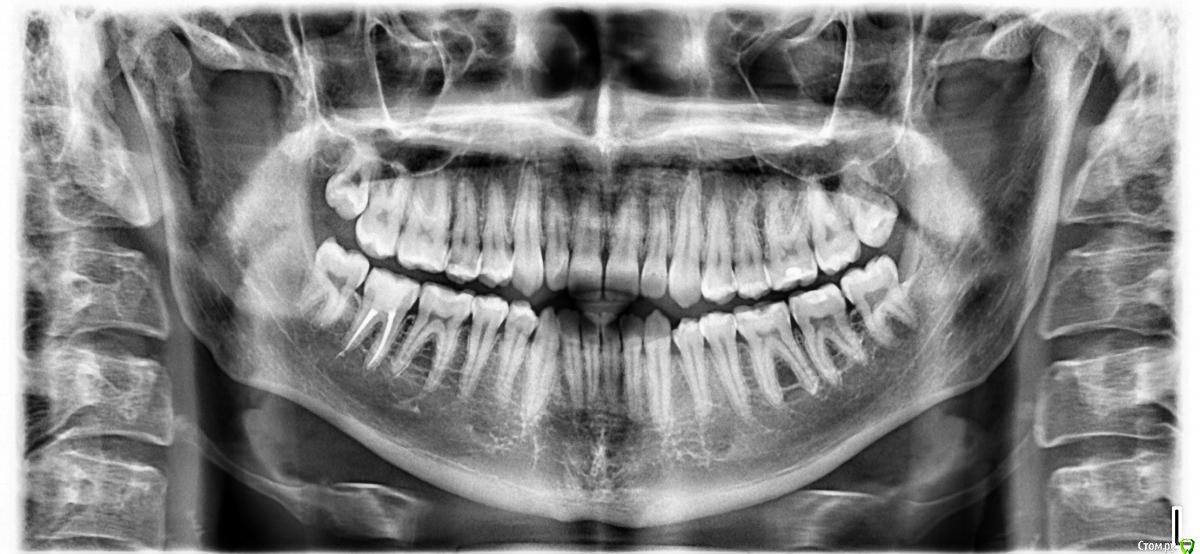

Nigthmore72 Опубликовано 8 февраля, 2019 Поделиться Опубликовано 8 февраля, 2019 Добрый день, что можете сказать о состоянии зубов в целом? Мне 22 года, у стоматолога последний раз был более 6 лет назад. Заранее спасибо. Ссылка на комментарий

shishok Опубликовано 11 февраля, 2019 Поделиться Опубликовано 11 февраля, 2019 Похоже на скрытую кариозную полость на 15 зубе(5 верхний правый). Ссылка на комментарий

red_butler Опубликовано 19 февраля, 2019 Поделиться Опубликовано 19 февраля, 2019 То есть, всё остальное в норме ?Этот снимок покажет только серьезные проблемы, для полной картины нужен очный осмотр. Я бы рекомендовал протезирование 4.7 (если он восстановлен пломбой) Ссылка на комментарий